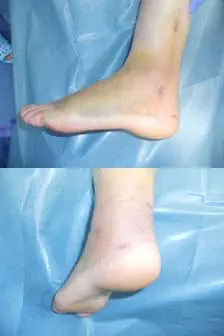

術後は下腿足尖ギプスを施行、2週でギプスカットし可動域訓練を開始、脛骨天蓋部骨折があるため4週より部分荷重、6週で全荷重を行った。術後8週の現在、可動域は底屈50°、背屈0°、全荷重歩行中である(図5)。